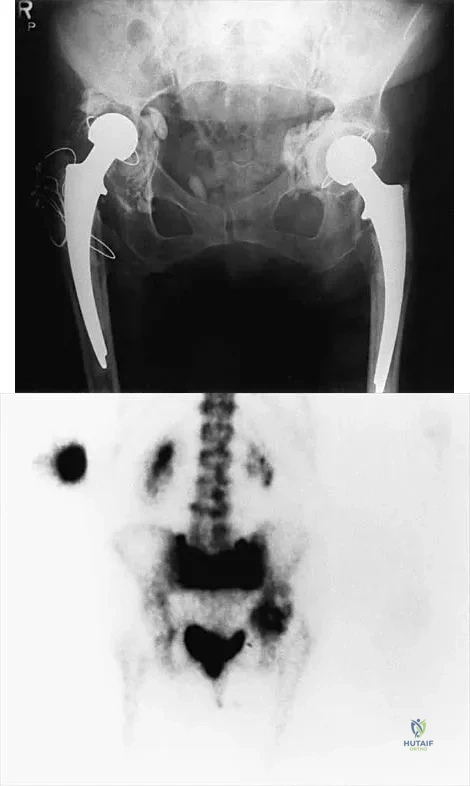

An 82-year-old woman reports right buttock pain after a car trip. Laboratory studies show an erythrocyte sedimentation rate of 30 mm/h and WBC of 4,600/mm3. Figure 34a shows a plain AP radiograph of the pelvis, and Figure 34b shows a delayed technetium Tc 99m bone scan. Management should consist of

Options:

- bed rest and pain medication.

- revision of the right acetabular component.

- revision of the right femoral component.

- revision of the right total hip replacement.

- resection arthroplasty.

Correct Answer: bed rest and pain medication.

Explanation:

The radiograph shows bilateral cemented total hip arthroplasties. The acetabular components are loose bilaterally, but there has been no acute change. Therefore, it is unlikely that the acetabular loosening is contributing to the patient's pain. The bone scan is consistent with a sacral insufficiency fracture. This is best treated with bed rest and pain medication. Activity can be increased as the pain allows. Revision will not address the pain. Newhouse KE, el-Khoury GY, Buckwalter JA: Occult sacral fractures in osteopenic patients. J Bone Joint Surg Am 1992;74:1472-1477.

References:

Marmor L: Stress fracture of the pubic ramus simulating a loose total hip replacement. Clin Orthop 1976;121:103-104.